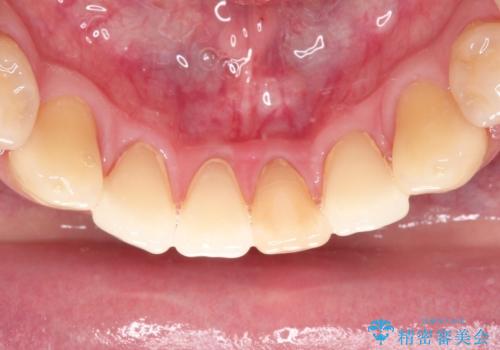

下顎前歯のセラミッククラウン

- 前歯の審美障害を主訴に来院されました。

根管治療を行なったのちオールセラミッククラウン(スタンダード)にて修復治療を行なっております。

歯髄壊死により変色した歯は根管治療が必要となります。